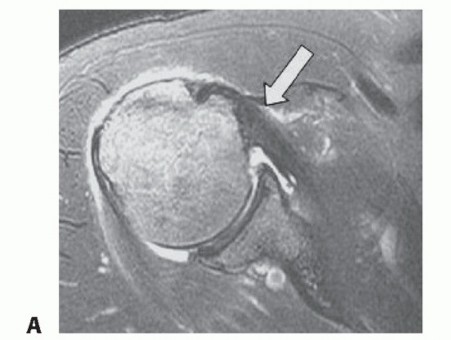

DEFINITION Subscapularis tears are less common than supraspinatus or infraspinatus tears. They occur in 2% to…

DEFINITION The subscapularis is one of four muscles making up the rotator cuff. Tears can result from chronic…